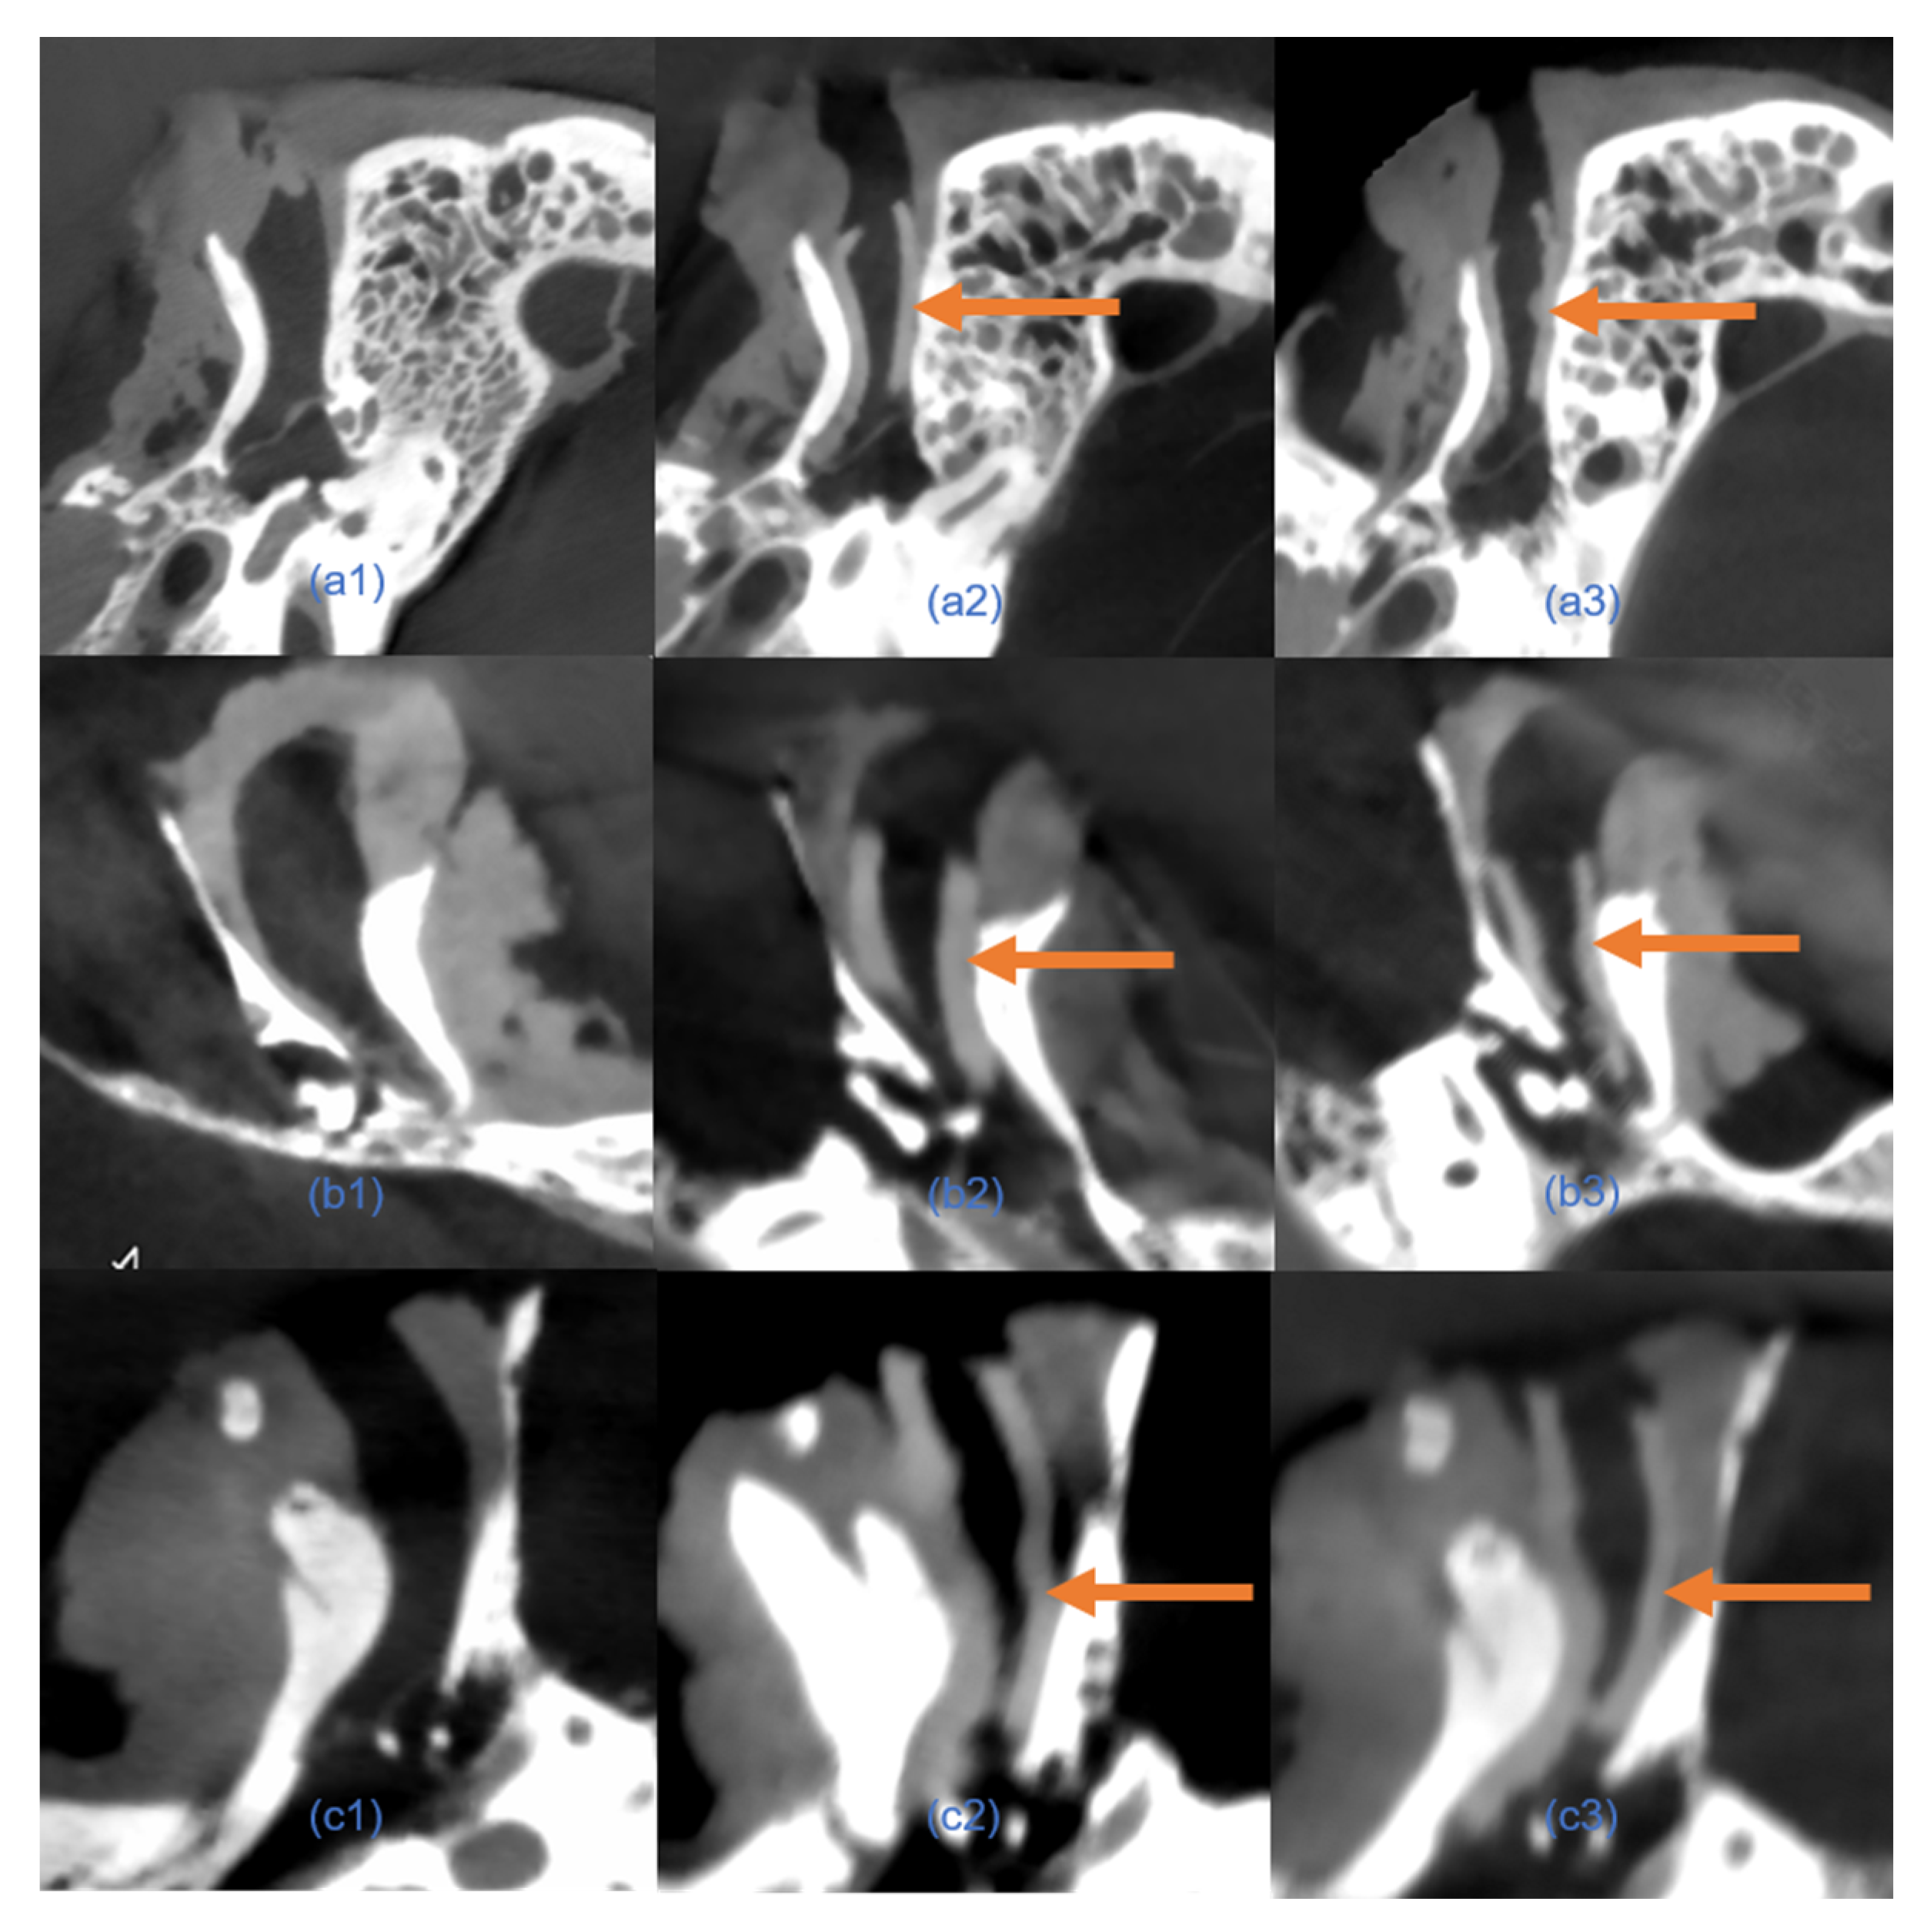

Figure 6. Comparison of 3D-printed EECI models generated from manual and automated segmentation methods. (a1a3) Three-dimensional models of EECIs derived from manual segmentation for temporal bone specimens 1, 2, and 3, respectively. (b1b3) Corresponding 3D models of EECIs generated using the custom automated segmentation plugin for the same specimens. (c1c3) Overlapping models illustrating the high degree of concordance between EECIs generated by the two methods for each temporal bone specimen.

We first evaluated the consistency of EECIs generated from manual and automated segmentation. Overlapping comparisons of the EECI models demonstrated high concordance between the two segmentation methods, as illustrated in Figure 6.

Quantitative analysis of the RMS surface distances revealed that the EECI models generated by manual segmentation exhibited RMS distances of 0.05 mm, 0.08 mm, and 0.06 mm relative to the EEC surface, while those generated by automated segmentation had RMS distances of 0.05 mm, 0.11 mm, and 0.12 mm. The results indicated a high degree of consistency and segmentation precision across both approaches (Figure 7). The otorhinolaryngologist rated all 3D-printed EECIs, regardless of segmentation method, as easily insertable and properly positioned. The performance evaluations for the insertion process are summarized in Table 3. Data are presented as mean values ± standard deviations. Specifically, all implants fit tightly against the bony walls of the EEC, with no visible gaps or misalignments along the edges (Figure 8). Post-insertion CBCT imaging further validated the fitting accuracy, demonstrating complete coverage of the EEC with no observable displacement or deformation of the implants (Figure 9 and Figure 10). In addition, the EECI models obtained by manual and automated segmentation before implantation demonstrated high spatial alignment and geometric consistency with the EEC model (Figure 11). Similarly, the comparison of EECI models before and after implantation, generated using both manual and automated segmentation methods, showed high geometric stability with minimal deformation, highlighting the accuracy and conformity of the implants. These findings indicate that the 3D printing and preparation process maintained high geometric accuracy, and no obvious deformation was observed after implantation. The RMS distances between the EEC model and the manually segmented EECI model after implantation were 0.22 mm, 0.18 mm, and 0.27 mm, while the RMS distances between the EEC model and the automatically segmented EECI model were 0.15 mm, 0.16 mm, and 0.22 mm, respectively (Figure 7). This further confirmed that the implant had high geometric stability and a close fit with the EEC.